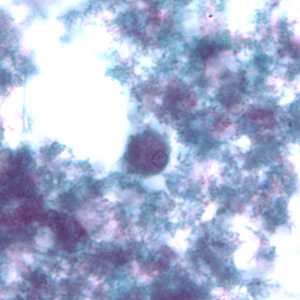

Figure A: Cysts of E. nana stained with trichrome.

Figure B: Cyst of E. nana stained with trichrome.

Figure C: Cyst of E. nana stained with trichrome.

Figure D: Cyst of E. nana stained with trichrome.